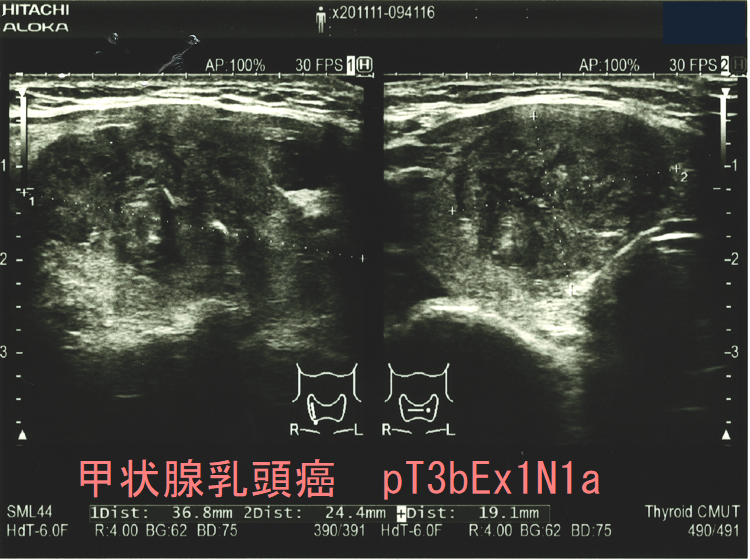

よって、それらのリスクを冒してまで予防的外側区域リンパ節郭清を行うのは、どの様な症例でしょうか?隈病院外科によると、

①甲状腺乳頭癌の大きさが

3cmを超えると術後10年のリンパ節再発率13%

3cm未満は2%

②Ex2(浸潤が被膜を越えEx1以外の組織、臓器におよぶ)の術後10年リンパ節再発率14%

Ex0(浸潤が被膜を越えない)あるいはEx1(浸潤が被膜を越えるが、胸骨甲状筋か脂肪組織に留まる)は5%

※Ex1a(周囲の脂肪組織に及ぶ)、Ex1b(前頸筋群、副甲状腺に及ぶ)

なので、3cm以上、またはEx2が予防的外側区域リンパ節郭清の適応になります。(日本内分泌・甲状腺外科学会雑誌 Vol. 29 (2012) No. 2 p. 123-125)